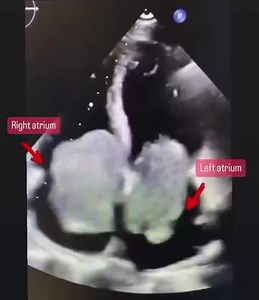

Carney Complex Explanation of the Condition: Carney Complex, also known as Carney syndrome, is a rare genetic disorder characterized by the development of multiple tumors in various parts of the body, including the heart. It is caused by mutations in the PRKAR1A gene. The condition is typically inherited in an autosomal dominant pattern, meaning that a person with one affected parent has a 50% chance of inheriting the condition. Clinical Features: Carney Complex can present with a wide range of

Carney Complex With Cardiac Myxomas